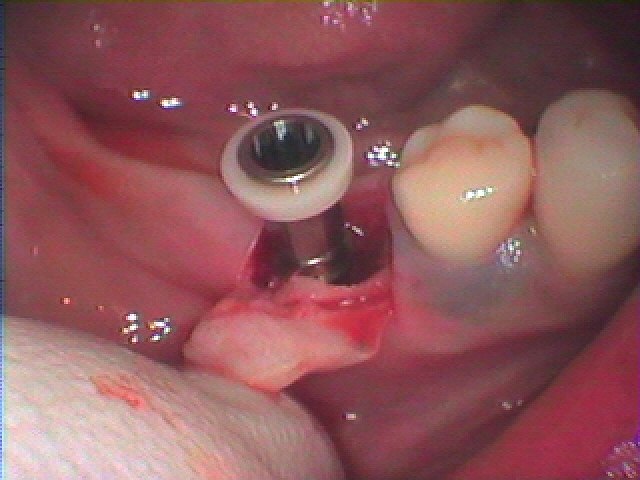

インプラント埋入時になります

骨補填材を転入して縫合して終了となります